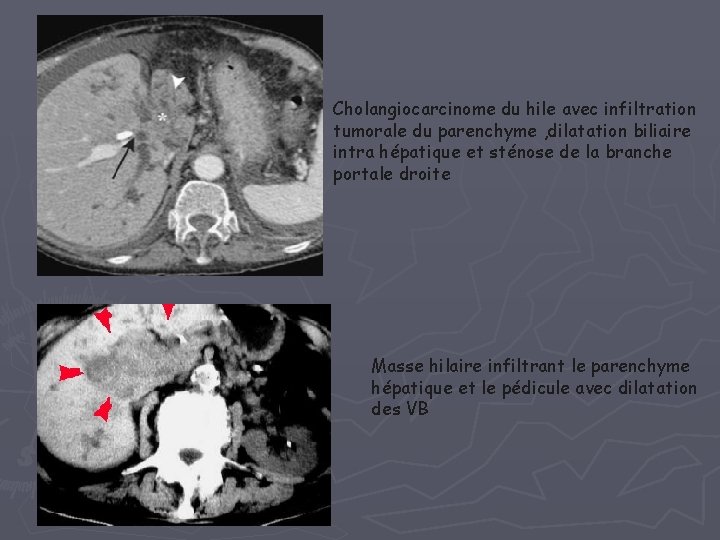

2 – Cholangiocarcinome hilaire - Adénocarcinome : 95% - tumeur rare de très mauvais Pc - facteurs de risque lithiases intra hépatiques , Mdie de Caroli, Cholangite sclérosante -ECHO : - 70% : dilatation isolée des VBIH avec arrêt brutal au niveau de la convergence hilaire - 3 formes: • infiltrante : épaississement circonférentiel de la paroi biliaire • nodulaire endoluminale : nodule échogène dans un canal biliaire dilaté • bourgeonnante extraluminale : masse hilaire ou pédiculaire hypo ou hyperéchogène mal limitée

-TDM : • Tumeur isodense < C • Rehaussement variable et tardif+++ • Bilan d’extension : vasculaire, GG, biliaire, et métastatique masse de la convergence fortement rehaussée avec dilatation des voies biliaires d’amont

Cholangiocarcinome du hile avec infiltration tumorale du parenchyme , dilatation biliaire intra hépatique et sténose de la branche portale droite Masse hilaire infiltrant le parenchyme hépatique et le pédicule avec dilatation des VB